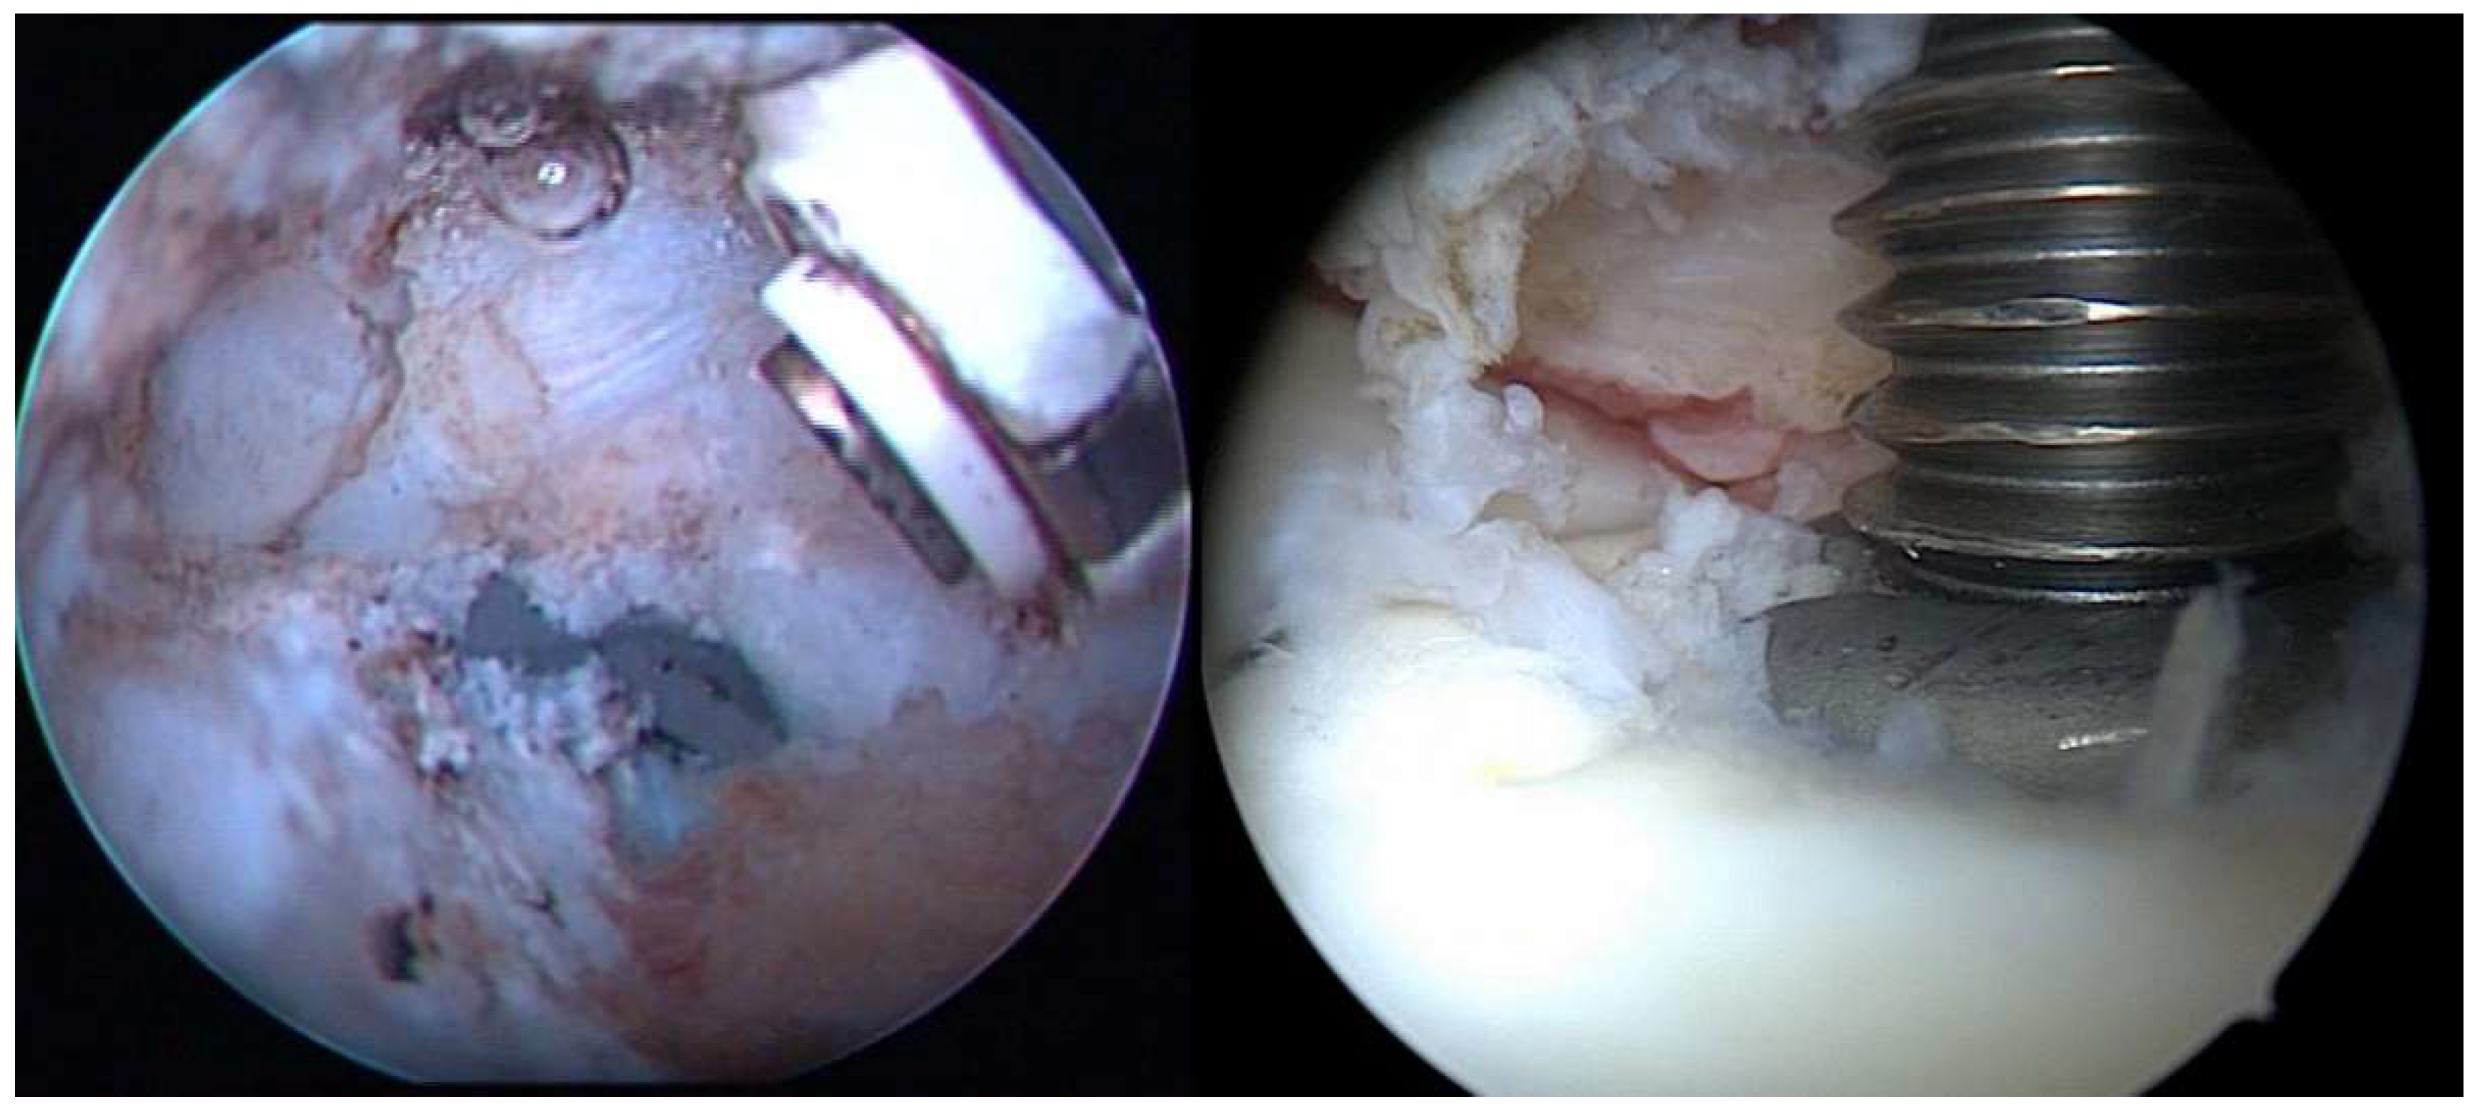

Figure 2.

Arthroscopic imagery. (left) Fibrous adhesions between the tendon of the supraspinatus muscle and the humeral head with a partially protruding end of the nail; (right) extraction of the protruding nail under arthroscopic control.